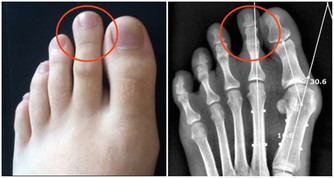

4、預防骨質疏鬆:秋葵的鈣質吸收率是牛奶的2倍!